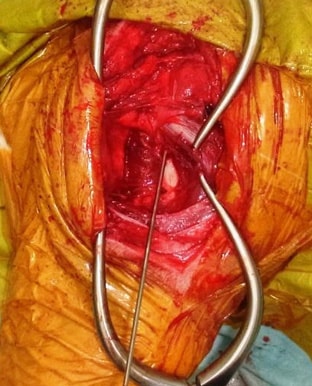

![]() 関節包が破れて大腿骨頭がむき出しになっています。  |

![]() 破れてしまった関節包の再建手術を行います。  |